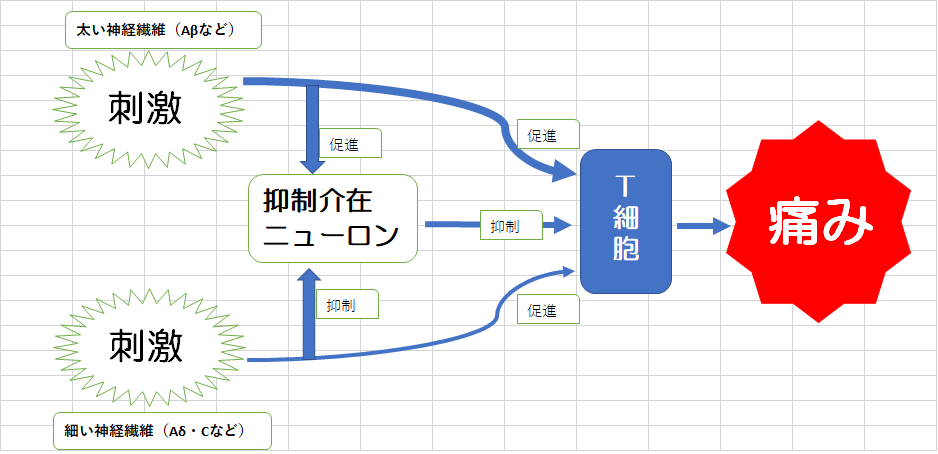

痛みの強さは、侵害情報を中枢へ伝達する「T細胞」への興奮性入力・抑制性入力のバランスによって決まります。

興奮性入力は細い神経線維であるC線維やAδ侵害受容求心性線維から、抑制性入力は太い神経線維であるAβ非侵害受容知覚求心性線維から、脊髄後根膠様質を介してT細胞に受け取られます。

ゲートコントロール理論では、脊髄後根膠様質にある「抑制介在ニューロン」が

T細胞を抑制させられると考えています。

抑制介在ニューロンを促進するには、抑制性入力を担う太い神経線維Aβを刺激する必要があります。

患部を撫でさするとAβが刺激され抑制介在ニューロンが促進され、痛みを伝えるT細胞を抑制するため。です。